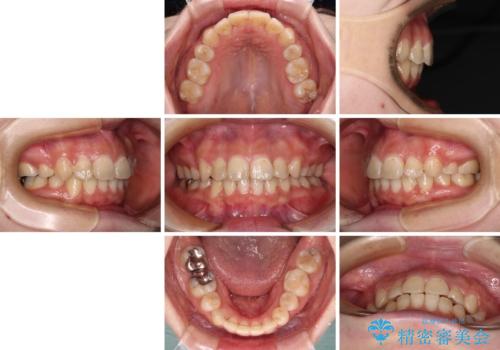

これほど顕著に裏側に隠れいてる歯ですと、仕上がったときに両隣の歯と軸に差が認められることが多いのですが、殆ど違和感のない歯並びを達成することができました。